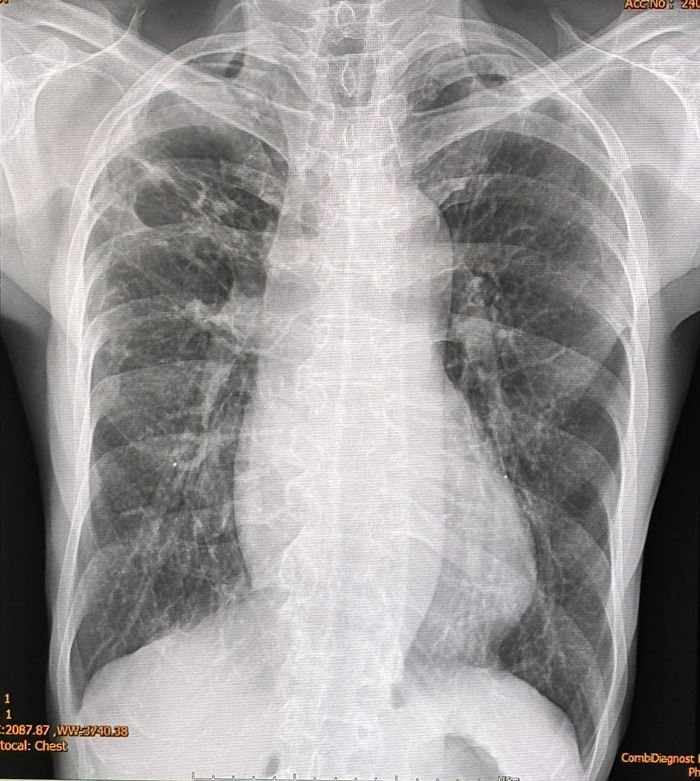

รายงานเผยว่า ผู้ป่วยเคยเป็นวัณโรคปอดเมื่ออายุ 25 ปี รักษาหายแล้ว แต่ในเดือนเมษายน 2567 ได้ไปพบแพทย์ที่โรงพยาบาลใกล้บ้าน ด้วยอาการเบื่ออาหาร น้ำหนักลด ไม่มีไข้ ไม่ไอ ไม่มีเสมหะ แต่เอกซเรย์ปอดผิดปกติ มีจุดและพังผืดที่ปอดข้างขวากลีบบน กลีบกลาง และปอดข้างซ้ายกลีบบน (ดูรูป)